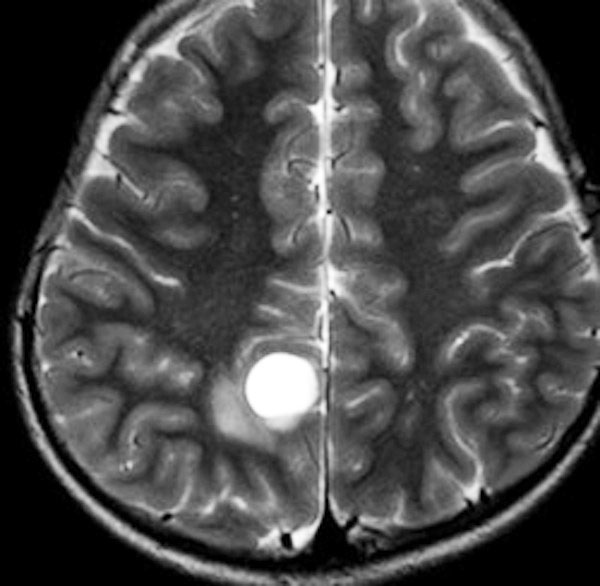

大脳皮質の毛様細胞性星細胞腫

小児期の右大脳頭頂葉にできた毛様細胞性星細胞腫です。小脳と同様に大脳にも壁在結節を作ってのう胞性増大する毛様細胞性星細胞腫というのはよくみかけます。てんかん(けいれん)発作で発症するものが多いです。腫瘍を摘出すると症候性てんかんが止まることが期待できます。治療方法は手術摘出です。腫瘍のある場所が深部で摘出術が神経脱落症状を招くと考えられる場合には,経過観察して,増大するようならガドリニウム増強される腫瘍実質部分にだけ,定位放射線治療することもあります。